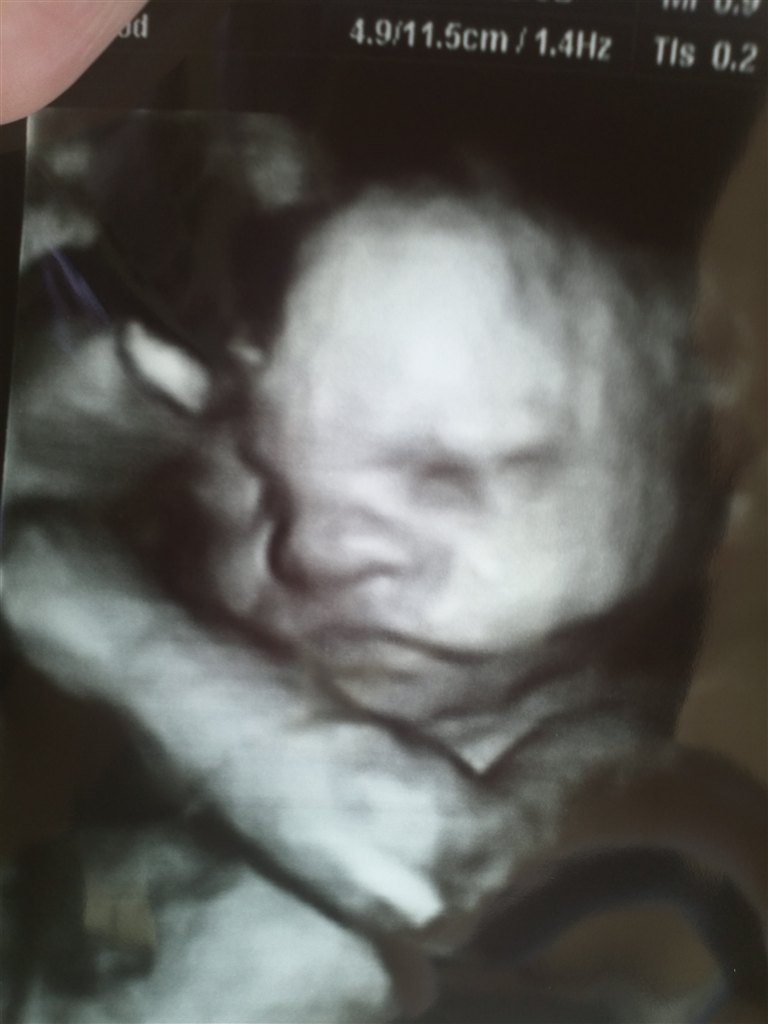

Billed 1 er 3d scanning ( lidt sjovt om i mener hun ligner)

Stoooort tillykke Det er da utrolig hvor godt et scanningsbillede I har fået -hun ligner jo seg selv!

Stort stort tillykke  Synes billedet passer godt

Synes det er meget tydeligt på 3D og så på det rigtige billede. Specielt på næse og mund;0)